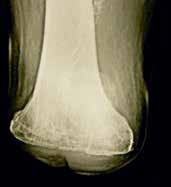

Bei der Operation selbst (Abb. 1–6) geht man so vor, dass zunächst ein zirkulärer Hautschnitt etwa 4 bis 7 cm unterhalb des Tibia-Plateaus erfolgt. Es ist besonders wichtig, darauf zu achten, möglichst viel Haut unterhalb des Gelenkspaltes zu belassen, weil in dieser Region die Haut sich erheblich retrahieren kann. Die Hautnaht muss aber unbedingt ohne Spannung erfolgen. Anschließend präpariert man am Patellaband hoch bis zum Gelenkspalt, eröffnet die Kapsel und durchtrennt dann sukzessive die Kreuzbänder und die Kapsel. Unter fortwährendem Zug am Unterschenkel wird sodann durch das Gelenk die Kapsel bis zur hinteren Kapsel durchtrennt. Dabei werden die auf der Knierückseite liegenden Strukturen geschont. Der Gelenkknorpel wird unberührt belassen. Die bradytrophen Menisci werden entfernt. Die Kniescheibe selbst wird nicht, wie immer wieder in Lehrbüchern beschrieben, an den Kreuzbandstümpfen fixiert, da hieraus oft eine Fehlpositionierung der Kniescheibe unter die Belastungsfläche resultiert. Die Kniescheibe ist in dieser Position nicht endbelastbar, sie verursacht Druckprobleme (s. Abb. 11) und schmerzt. Zudem resultiert hieraus eine Verlängerung des Stumpfes.

Eine exzessiv hypermobile Kniescheibe verursacht in der Prothesenversorgung sekundäre Probleme. Hier ist der Orthopädie-Techniker gefordert. Meist lässt sich eine stark bewegliche Kniescheibe durch eine Art Laufrinne in der Prothese gut in den Griff bekommen. In seltenen Fällen ist eine Entfernung der Kniescheibe notwendig. Auch bei erheblichen retropatellaren Degenerationen ist bereits bei der primären Operation, in seltenen Fällen sekundär die Entfernung der Kniescheibe angezeigt. Gleiches kann aus einer in der Operation zu tief festgenähten Kniescheibe resultieren (Abb. 11).